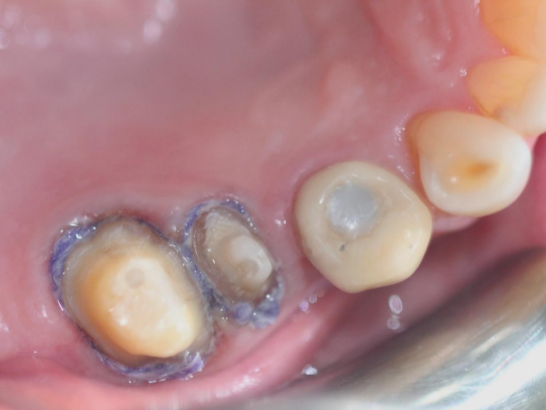

Case i

Case ii

Step 4: Place the second retraction cord in the gingival sulcus

Choose a retraction cord that fills the gingival sulcus. It can be observed that the retraction cord completely surrounds the tooth. The second retraction cord often needs to be impregnated with hemostatic material.